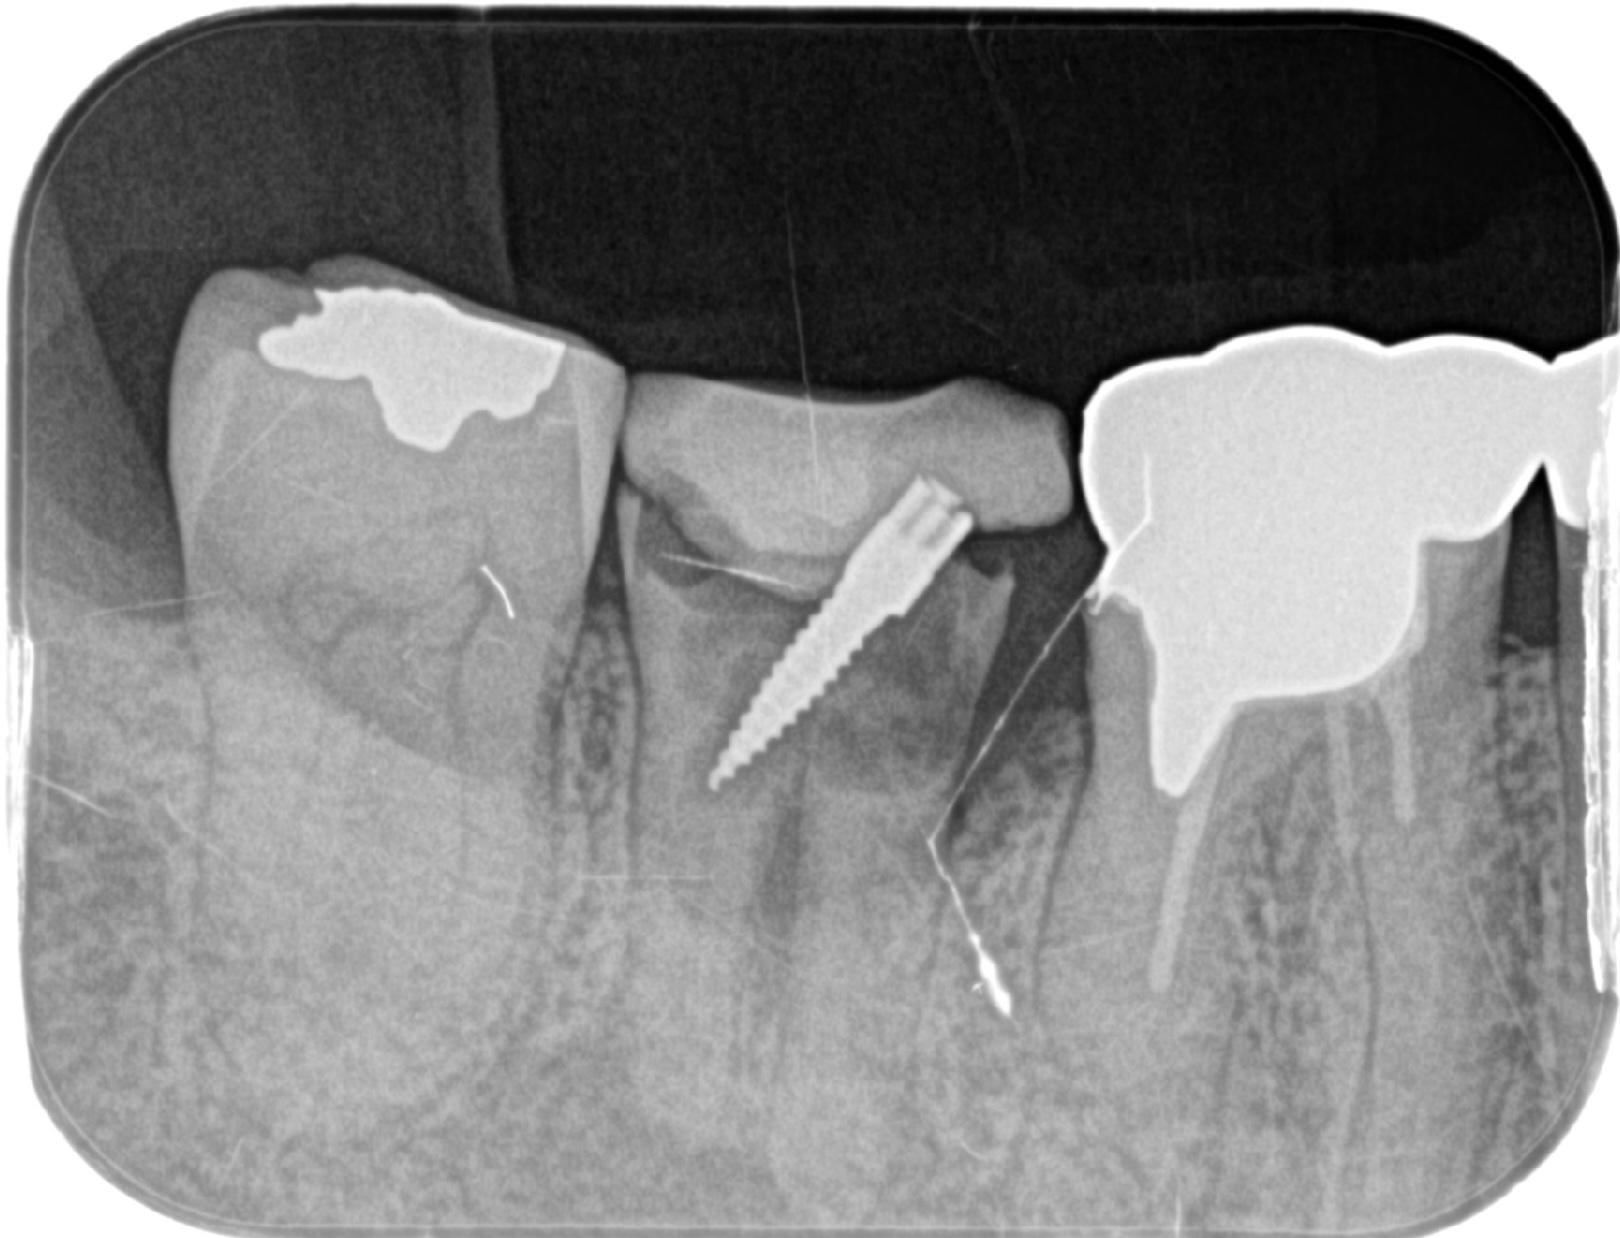

右下奥歯を1本インプラント治療した症例

| 治療内容 | スクリューポスト不適合で、根尖病巣も大きく残すことが難しいため抜歯しインプラント治療へ。 歯槽骨の量が不足している場合に、人工骨や自家骨を移植し、特殊な膜で覆うことで骨の再生を促し、インプラントを埋入できるようにするGBRという治療法も併用。 |

| 抜歯部位 | 右下7 |